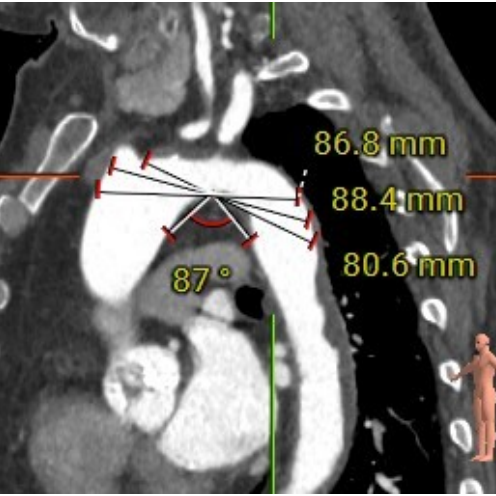

CT分析

主动脉根部结构

手术策略采用右侧股动脉为主入路,全麻配合食道超声进行。根据瓣环测量数据,初步确定选择Evolut PRO 29mm瓣膜。是否需要针对Type0型二叶瓣采用downsize策略,团队进行了详尽探讨,决定先行20mm球囊扩张,根据球囊形态和瓣周漏情况决定最终选型。